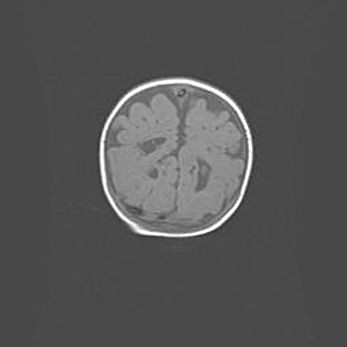

Неполная лизэнцефалия (пахигирия). Открытая гидроцефалия.

Возраст: 17 дней

Вес: 3110 г

Пол: мужской

Окружность головы: 33,5 см

Срок гестации: 35-36 недель

Лизэнцефалия—недоразвитие корковой пластинки и мозговых извилин в результате нарушения миграции нейронов коры. Поверхность мозговых полушарий гладкая. Микроскопически выявляется отсутствие нормальных слоев коры и скопление групп нейронов в подкорковом белом веществе.

Пахигирия—уменьшение числа вторичных извилин. В пораженном полушарии нервные клетки образуют толстый недифференцированный слой с неправильно расположенными нервными волокнами и группами гетеротопных клеток. Нервные клетки незрелые. Белое вещество истончено. При этом нередко аномально развит корково-спинномозговой путь.